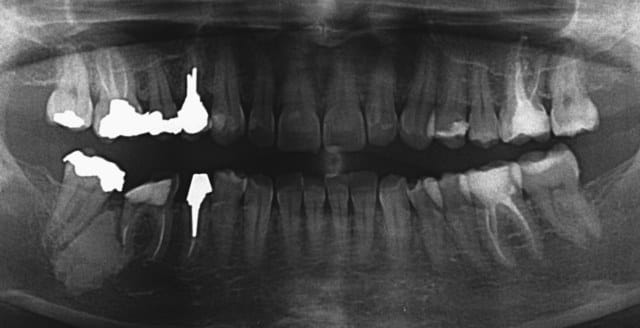

C'est quoi, cette lésion osseuse en distal de 46?

Je précise qu'il existe une lyse radiculaire sur la racine distale de 46.

je seche...en tous cas c'est du a la racine distale ( ou son traitement ) de 46...

C'est bizarre, ça a presque la forme d'une dent, ça ne serait pas un odontome des fois ? (pas tapper)

Oui, effectivement la forme rappelle celle d'une dent. Mais je n'ai pas l'impression que ce soit un odontôme.

Femme, 44 ans. RAS santé générale. Malocclusion avec mastication unilatérale droite (en rapport avec la lésion?).

On peut penser de prime abord à une ostéite condensante ou à une ostéosclérose; 46 étant non vitale, on pencherait pour une ostéite condensante due à une infection suopposée de la racine distale de 46. A vérifier bien sur.

je pense pas que ca soit un osteoblastome. il y a une zone radioclaire autour d habitude et il se developpe autour des racines qui se resorbent. La ca me parait bien décalé par rapport aux racines. En revanche ca a respecté le ligament de la 7. Généralement un ostéoblastome provoque une voussure de la corticale.

La patiente ne mastique que du côté lésion depuis toujours (articulé transversal exagéré, donc pas de contacts molaires à gauche). Je n'ai pas de parapicale. Rien à la palpation, pas de douleurs.

Le diagnostic entre ostéite condensante et ostéosclérose est surtout étiologique:

-surcharge fonctionelle évoquée pour ostéosclérose: là elle est présente

-infection radic pour ostéite condensante: là elle est possible mais non visible.

L'Ostéosclérose prend la tête.

le cémentoblastome est bordé par une zone radioclaire.

La dysplasie cémentaire, ou cémentome, fibrocémentome, est en général périapicale, souvent arrondie, en général moins de 1 cm, et elle est encapsulée.

Pour résumer : très probable odontome banal, totalement bénin, ne rien faire ni même de biopsie, simple surveillance clinique et radiographique 1 fois par an...